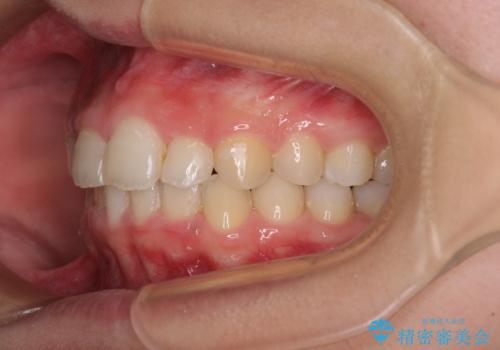

- 前歯の歯並びと不自然な色をした前歯のクラウンを気にして来院された患者様です。

上下前歯の歯列不正はインビザラインにより歯列を整え、その後に、前歯をオーダーメイドタイプのオールセラミッククラウンにて補綴治療することとしました。

前歯のデコボコを一番気にしていらっしゃいましたが、矯正治療により下顎前歯が隠れるほどのディープバイトも一緒に改善され、奥歯に負担のかかりにくい咬み合わせとなりました。